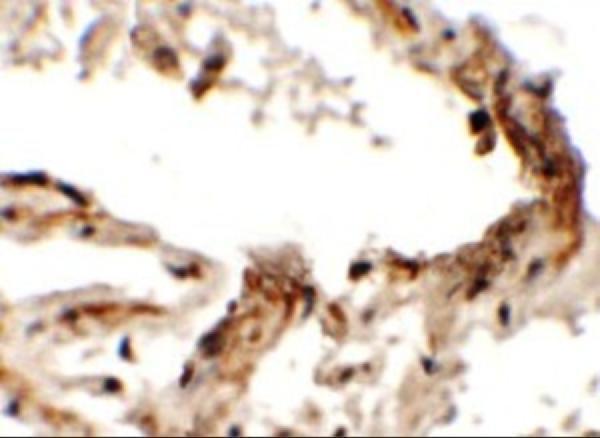

Cerebral cortex.

Nucleus.